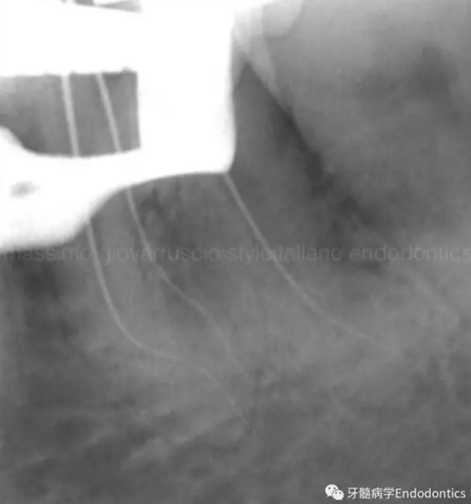

圖9.當遇到了根尖方向的阻力,退出銼,使用銼預彎鉗(Endobender)平滑的預彎銼尖部的2mm,將銼上的硅膠止動片的方向指示調成朝向銼彎曲的方向,這樣你就可以繞過障礙形成通路了。

圖10.探查時小心地使用給手表上發(fā)條的動作使銼向前通過障礙。遇到阻礙時,稍微回拉銼,將銼尖轉向新的方向,向根尖方向扭動,觀察銼是否前進。如果沒有,將銼回拉,重新將彎曲的銼尖改變方向,觀察是否通過。不斷重復,觀察是否前進,直至通路形成。必須使用根測儀和X線片檢查在障礙通過后是否到達了根尖止點。